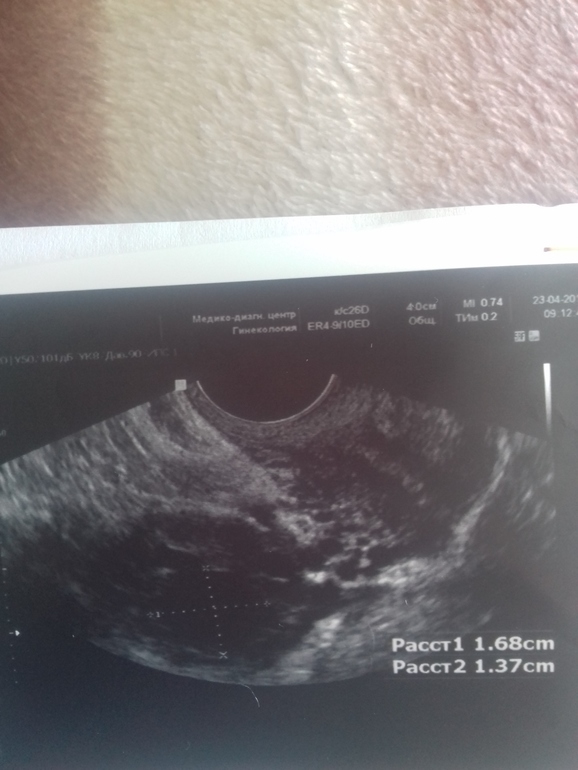

Всем доброго утра. Девочки мои дорогие,что можете сказать. Сегодня 15 д.ц. сходила на узи в другую клинику. Итог:фолликул 14×16.68 и эндометрий с 5 до 10 поднялся за 2 дня. Не знаю то ли ананасы помогли,то ли дивигель,но факт остается фактом. Фолликул растет медленно. Если на 13 д.ц. был 14×15мм. Это нормально вообще. А то за фоллик свой переживаю.